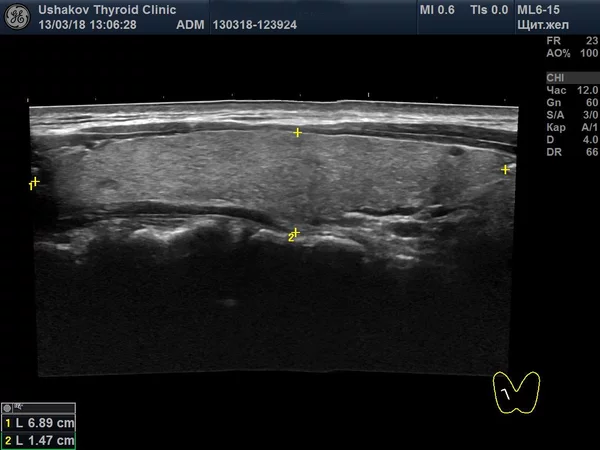

Другой поразительный пример: почти полное восстановление доли железы у 13-летней пациентки, после того как хирург оставил лишь 10% её исходного объёма. Молодой возраст и сохранённый небольшой участок ткани позволили запустить мощный регенеративный процесс.